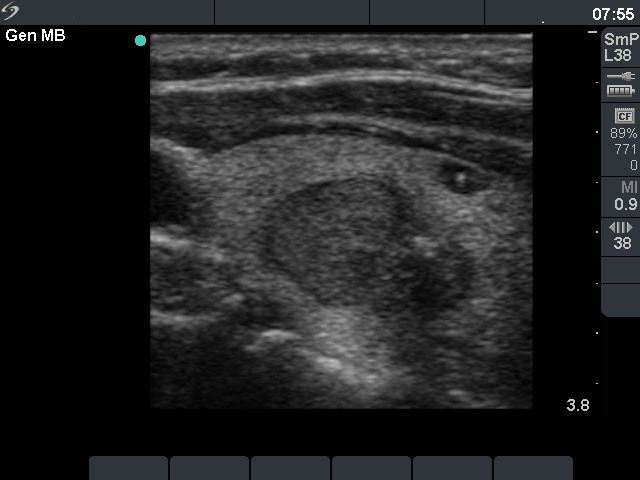

Ultrasonography: the thyroids were echonormal. There were two hypoechoegenic nodules next to each other in the left lobe. The upper had regular shape and presented a type 2 vascular pattern while the lower one had irregular borders, contained microcalcifications. The volume of the former nodule increased by 38% and the latter suspicious one by 72% over the previous 5 years.

Cytological diagnosis (from the irregular nodule): papillary cancer.

Histopathology: three distinct entities - a papillary microcarcinoma with a maximal diameter of 9 mm according to the nodule aspirated, an oxyphilic adenoma according to the other nodule and several hyperplastic nodules in both thyroids.